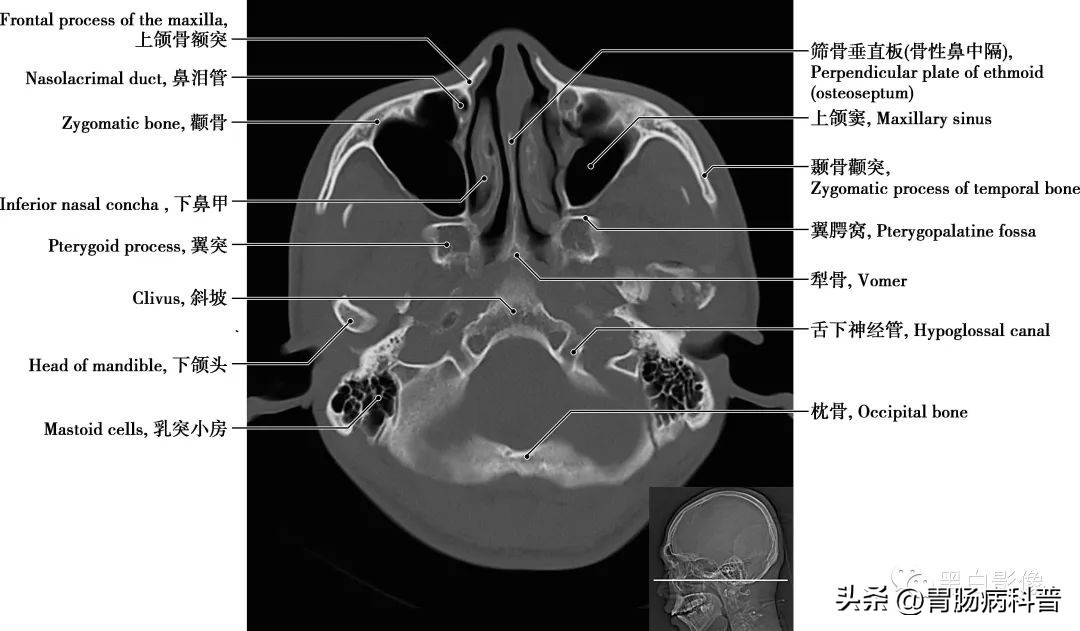

图1-2-19 经小脑扁桃体轴位切面

上颌窦 上颌骨体内的锥形空腔,位于上颌骨体内,窦壁为骨质,窦壁覆黏膜,向内侧开口于中鼻道,分为一底、一尖及前、后、上、下四个壁。由于窦口高于窦底部,故在直立位时若有炎性物不易自然流出。鼻泪管 为一膜性管道,上部包埋在骨性鼻泪管中,与骨膜紧密相结合;下部在鼻腔外侧壁黏膜深面,下部开口于下鼻道外侧壁的前部